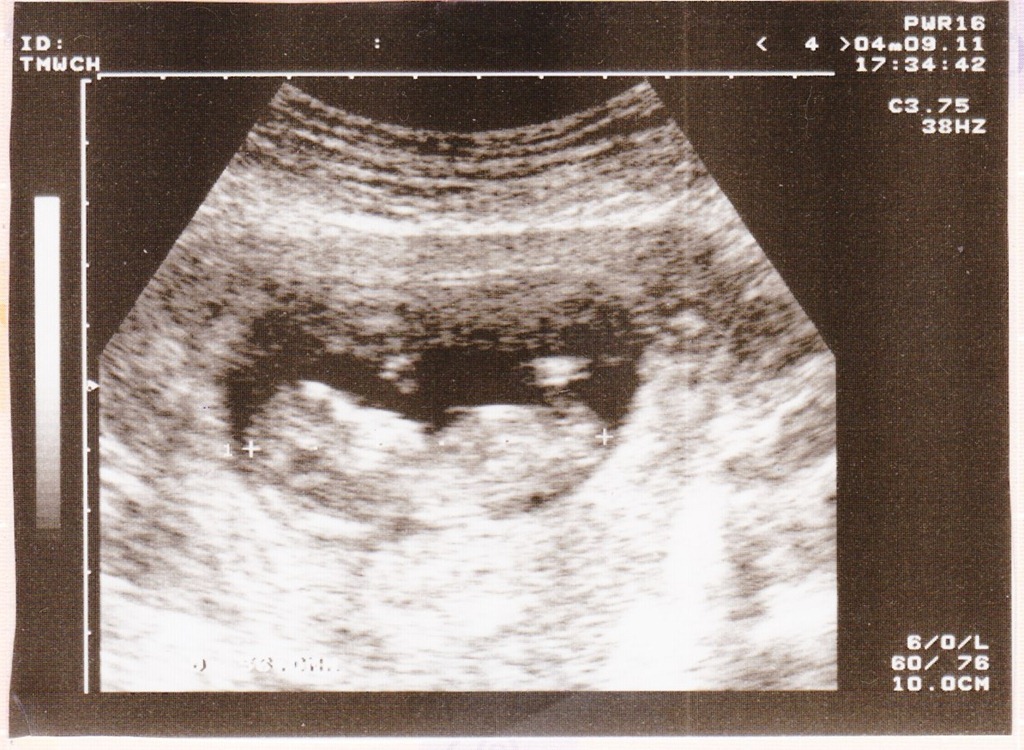

驗孕棒驗出結果後,媽媽馬上去做產檢,這時候我4周大,雖然驗孕棒複檢的確有懷孕的跡象,但是照腹部超音波時,醫生伯伯在媽媽子宮裡卻還看不到我,一方面是因為我還很小,另一方面也擔心子宮外孕的可能性,所以請媽咪耐心等待我的長大。5周了,在子宮裡還是看不到,媽媽開始有點緊張;近6周大時,腹部超音波終於確認我在子宮裡順利著床長大,這時候只有0.5cm。確認我在媽媽肚子裡安全的待著,爸爸媽媽鬆了一口氣也很感動,兩周來的擔心終於卸下,並陸續將懷孕的消息告訴了家人們。之後醫生伯伯推估預產期應該會是10月23日;這樣反推起來,是參加完仔仔爸比媽咪的婚禮後,才有了我的存在阿~